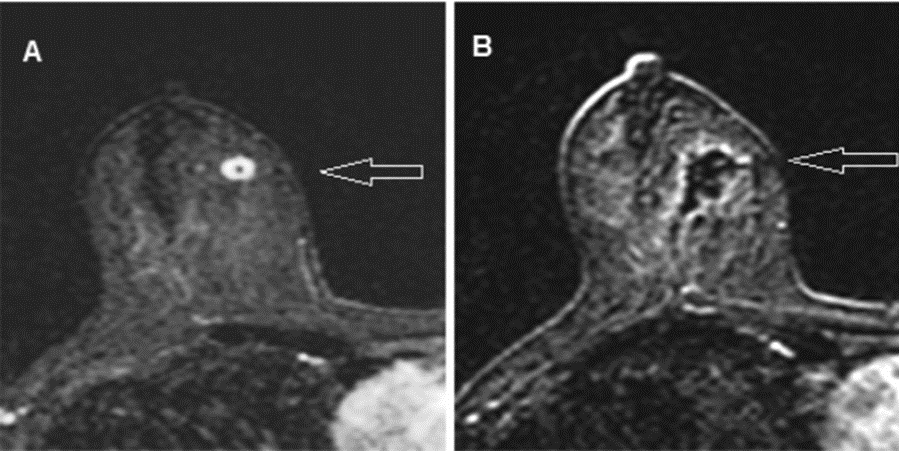

乳腺结节

激光消融技术用于乳腺结节的治疗,通过热效应实现组织凝固和坏死。无手术切口,避免瘢痕形成。最大限度减少正常组织损伤,适用于多灶性病变。

(图片来自网络)

(Schwartzberg et al., 2018 )